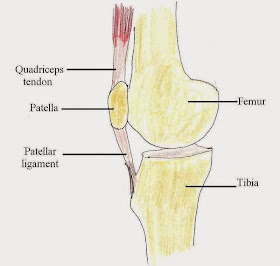

He was just starting his growth spurt. Youth athletes are vulnerable to a different class of injuries than adult athletes. The patellar ligament is what I call a structural complex, connecting the lower portion of the knee cap (the inferior pole of the patella) to a small bump on the shin called the tibial tuberosity.

This patellar ligament complex can be injured in different locations, depending on age:

- Age 11-12- at the inferior pole of the patella, an injury called Sinding-Larsen-Johannson syndrome

- Age 13-14- at the tibial tuberosity (where the patellar ligament attaches to the tibia)- called Osgood Schlatter syndrome.

The age ranges for SLJ and OS are approximate, but as a general rule SLJ occurs earlier in adolescence, and the more common OS occurs a few years later. Their timing is based on when the bony processes, called an apophysis, fuses to the rest of the bone.

By late adolescence, the apophyses have fully fused, so we don't see these injuries much by an athlete's late 20s. We may still see irregularities in the bone, but these are remnants of a prior injury, and rarely the cause of injury itself. Instead, in athletes who are past puberty, the most common site of injury is within the patellar ligament itself (usually closer to the patella than the tibial tuberosity), a a condition called patellar tendinopathy, or jumper's knee.